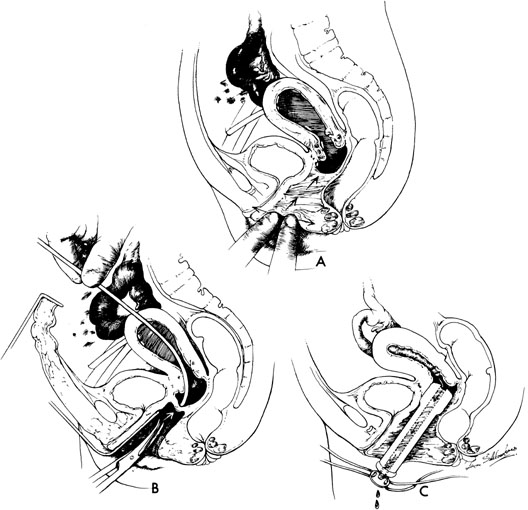

In some instances, however, the length of the obstructing transverse vaginal septum may be such that reanastomosing the upper and lower vagina is not possible. This is particularly true when one encounters a high transverse vaginal septum (Fig. 10). In this situation, a space is created between the rectum and the bladder so as to identify the obstructed upper vagina. It is important to distinguish the mass from the bladder anteriorly and the rectum posteriorly. This identification may be facilitated by the mass, which has resulted from accumulated menstrual blood. If one cannot be certain, however, exploratory laparotomy may be performed and a sound passed through the fundus of the uterus to tent the vaginal septum and allow the operator from below to incise and resect it safely (Fig. 11). In most instances, it is possible to identify the obstructing membrane, and the operator may then probe the mass with an aspirating needle to identify old menstrual blood. The upper vagina may then be opened and the septum excised. Because reanastomosis of the vagina cannot be performed, an indwelling lucite form is placed into the vagina. This form consists of a bulbous end and a channel through which menstruation may occur. This form may be held in place with a retaining harness. In most instances, the bulbous end of the form is retained in the upper vagina. This form should be left in place for 4 to 6 months. It is anticipated that epithelialization from the lower and upper vagina will have joined by proliferation of the epithelium. Following removal of the lucite form, vaginal dilation on a daily basis may be necessary for 2 to 4 months to prevent contracture.

Fig. 11. High transverse vaginal septum. A. The neovaginal space is opened with digital manipulation. B. If the mass cannot be identified from below because of its high position, it may be necessary to perform an exploratory laparotomy. A metal sound may be passed through the uterus to tent out the septum so that it may be incised. avoiding damage to the rectum or bladder. C. The lucite form is then placed in the upper vagina and secured with rubber straps.